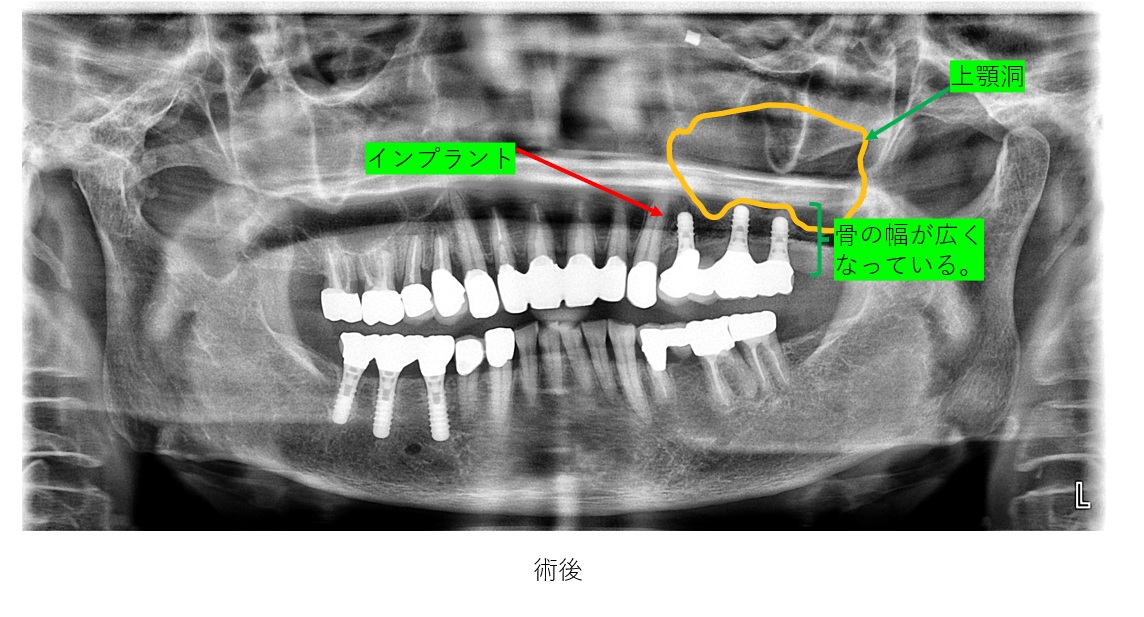

サイナスリフトを行ってから、6か月ほど置くと、左の上顎洞の直下に新しい骨が新生してきます。

術後6か月ほどすると左上の写真のように新しい骨ができております。

今回は、3本のインプラントを左上奥歯に埋入予定です。

インプラント埋入を上記のように3本正確に埋入出来ました。

左上に上顎洞直下にインプラントを埋入されているレントゲンです。